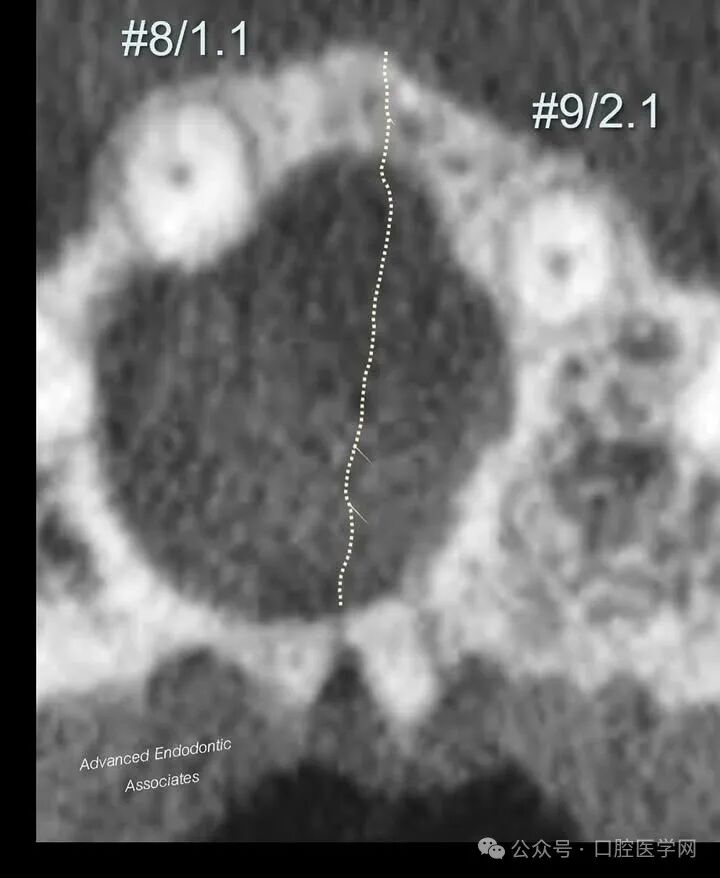

2. 跨越中线的特征:透射区可见跨越中线,这一表现不符合牙源性病变的典型特征。牙源性病变(LEOs)极少出现跨越中线的情况,仅在严重或广泛性感染病例中可能发生。

结合上述影像学特征及CBCT评估,我们明确诊断为“切牙管囊肿”。患者随后被转诊至口腔颌面外科医生处,进行进一步随访及治疗。